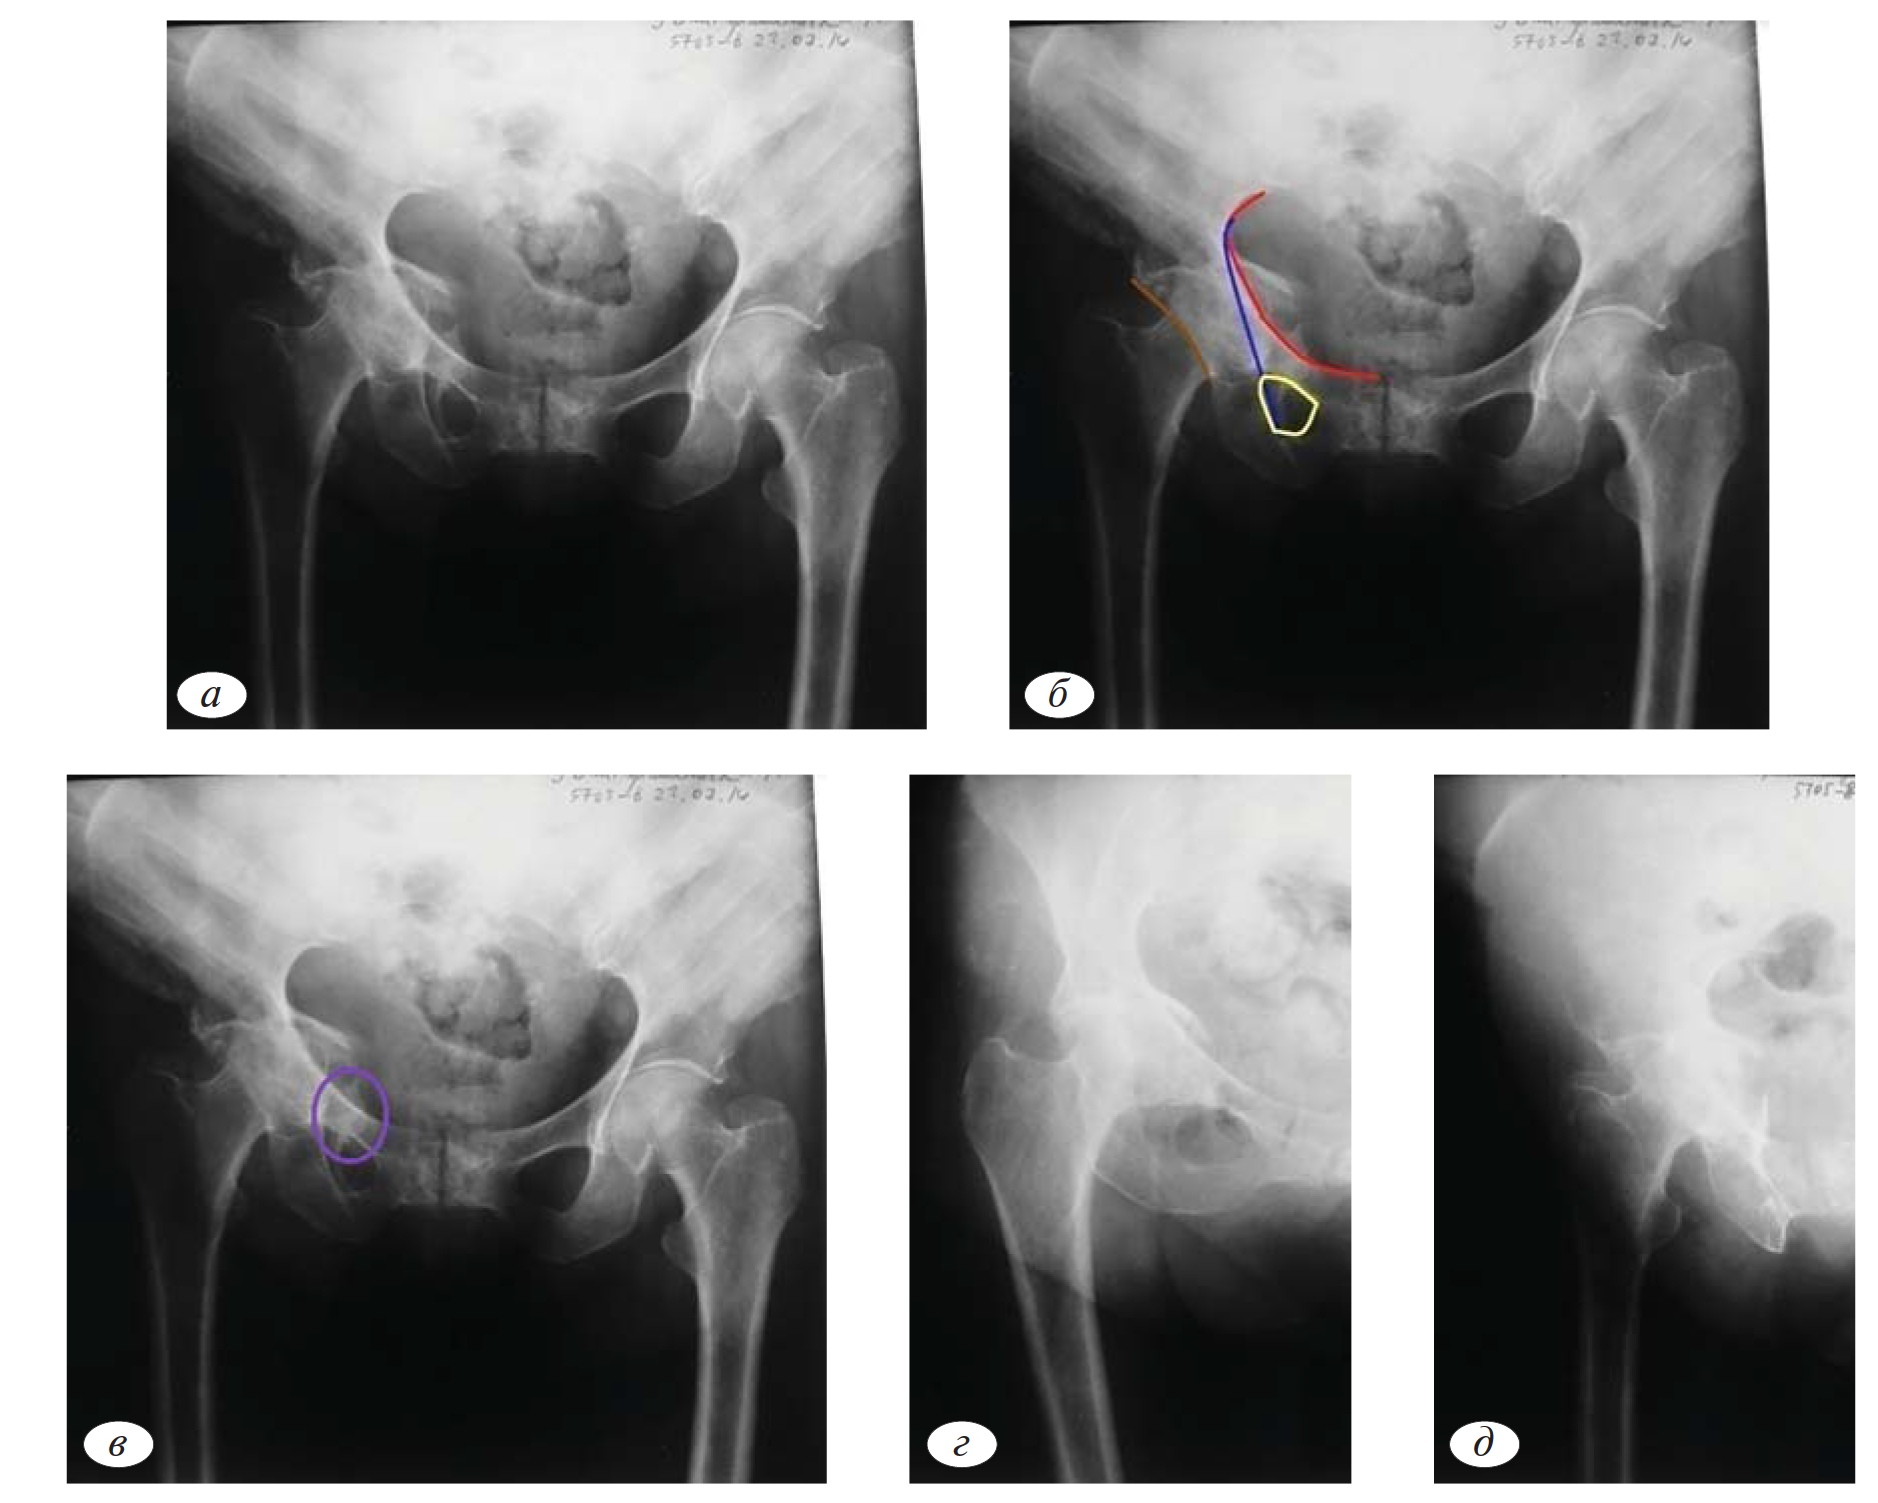

Наблюдение №2

В следующем клиническом примере на рентгенограмме таза в переднезадней проекции мы определяем целостность 4 основных референтных линий: подвздошно-гребешковая, подвздошно-седалищная, контуры запирательного отверстия, задняя стенка (рис. 2, а). На первом этапе диагностики мы исключили все возможные 10 типов по классификации Judet—Letournel, однако на рентгенограмме определяется центральное смещение головки бедренной кости и наличие отломков вне контуров референтных линий (рис. 2, б).

Обращает на себя внимание разрушение фигуры слезы. Анатомически это объясняется локализацией повреждения в передненижних отделах вертлужной впадины. Соответственно, хорошо различимые смещенные костные отломки представляют собой часть четырехсторонней пластинки, которая является дном вертлужной впадины (рис. 2, в).

Выполнение прицельных рентгенограмм позволяет нам подтвердить целостность анатомических структур, формирующих референтные линии (передняя и задняя колонны, края впадины). Наличие центрального вывиха головки бедренной кости характерно для переломов с поперечной линией излома, когда головка бедренной кости вклинивается между подвздошной костью и лобково-седалищным сегментом. В данном случае на рентгенограммах в подвздошной и запирательной проекции отчетливо определяется протрузия головки бедра в таз в проекции четырехсторонней пластинки, что подтверждает перелом дна вертлужной впадины (рис. 2, д).

Следует отметить, что повреждение четырехсторонней пластинки характерно для переломов на фоне остеопороза.

Рис. 2.а — обзорная рентгенография таза при поступлении; б — первый этап определения атипичного перелома четырехсторонней пластинки; в — окончательное определение атипичного перелома четырехсторонней пластинки; г, д — детализация перелома четырехсторонней пластинки с помощью прицельных рентгенограмм в запирательной и подвздошной проекции.